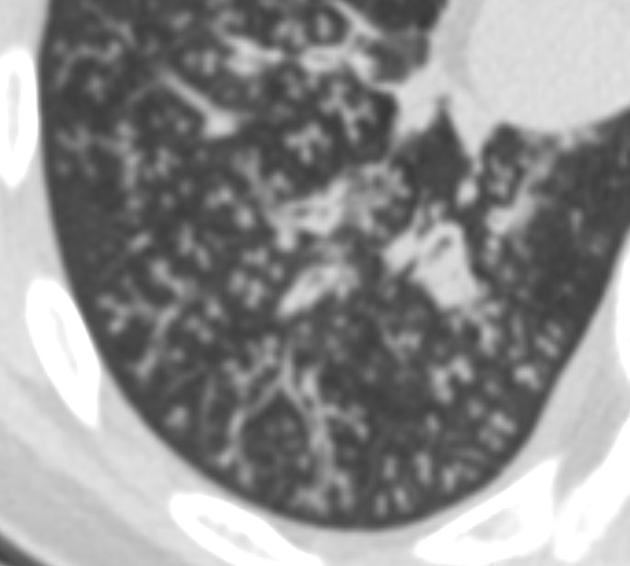

What is this pattern?

What is the etiology?

What disease processes can cause it?

Tree in bud pattern.

Caused by bronchiolar impaction and dilation by pus/mucus/fluid/inflammatory exudate.

Nonspecific- mostly caused by infections/inflammatory conditions. Possibilities include: active TB, MAI, viral pneumonia, fungal pneumonia, obliterative bronchiolitis, cystic fibrosis, immotile cilia syndrome, RA, and neoplastic.